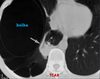

Enfisema para-septal com bolhas na TCAR

Enfisema Para-septal com bolhas (TCAR)

Enfisema para-septal - TCAR